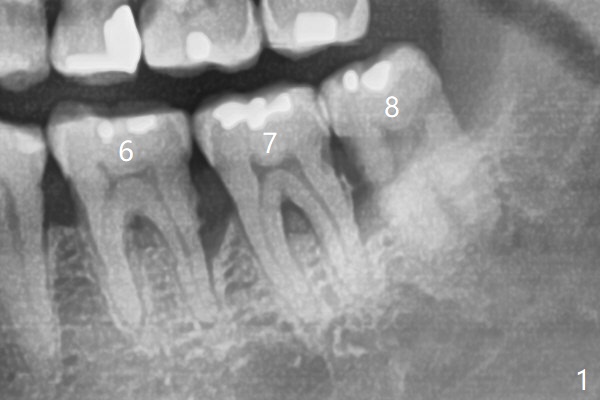

60岁男,吸烟,口腔卫生不好,不积极配合治疗,下前牙两个植体螺纹暴露,但是没有症状。两年中,左下七(图一,二)不能保留(图三),虽然六远中结石被清除(图三>),七位点保留(图四 *)时未能顺便在六远中填入骨粉(用血混合,胎盘膜覆盖)。四五个月后,七种植时将钻头骨粉放置于六远中缺损处,如何才能让骨粉在患处生根发芽?术后一个月,去除树脂敷料后,最表面骨粉未能被整合,下面骨粉好像已经与肉芽组织结合了(图五),其实根尖片应该拍摄证实这一点。吸烟者血供不好,愈合欠佳。术后三个月牙槽嵴宽(图六);高度稍微减低(图七)。术后4个月CT显示近中牙槽窝正好位于缺牙区正中(图八),所以植体必然进入近中窝(图九)。